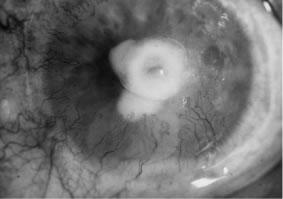

Candida infection typically produces epithelial ulceration, focal necrotizing stromal inflammation, moderate cellular infiltrate and edema in the adjacent stroma, and mild or moderate iritis in the early stages, indistinguishable from bacterial keratitis (Figs. 15, 16, and 17). Fungal elements cannot be detected by biomicroscopy. If untreated, the keratitis evolves to produce dense suppuration and necrosis of the deep stroma. Although multifocal suppuration may develop in polymicrobial keratitis, there is no distinctive sign of mixed Candida and bacterial infection (Fig. 18).

Fig. 15. C. albicans keratitis in an eye following chronic use of corticosteroid drops for herpes simplex keratitis. Note the central suppuration and perforation, endothelial plaques, and hypopyon.